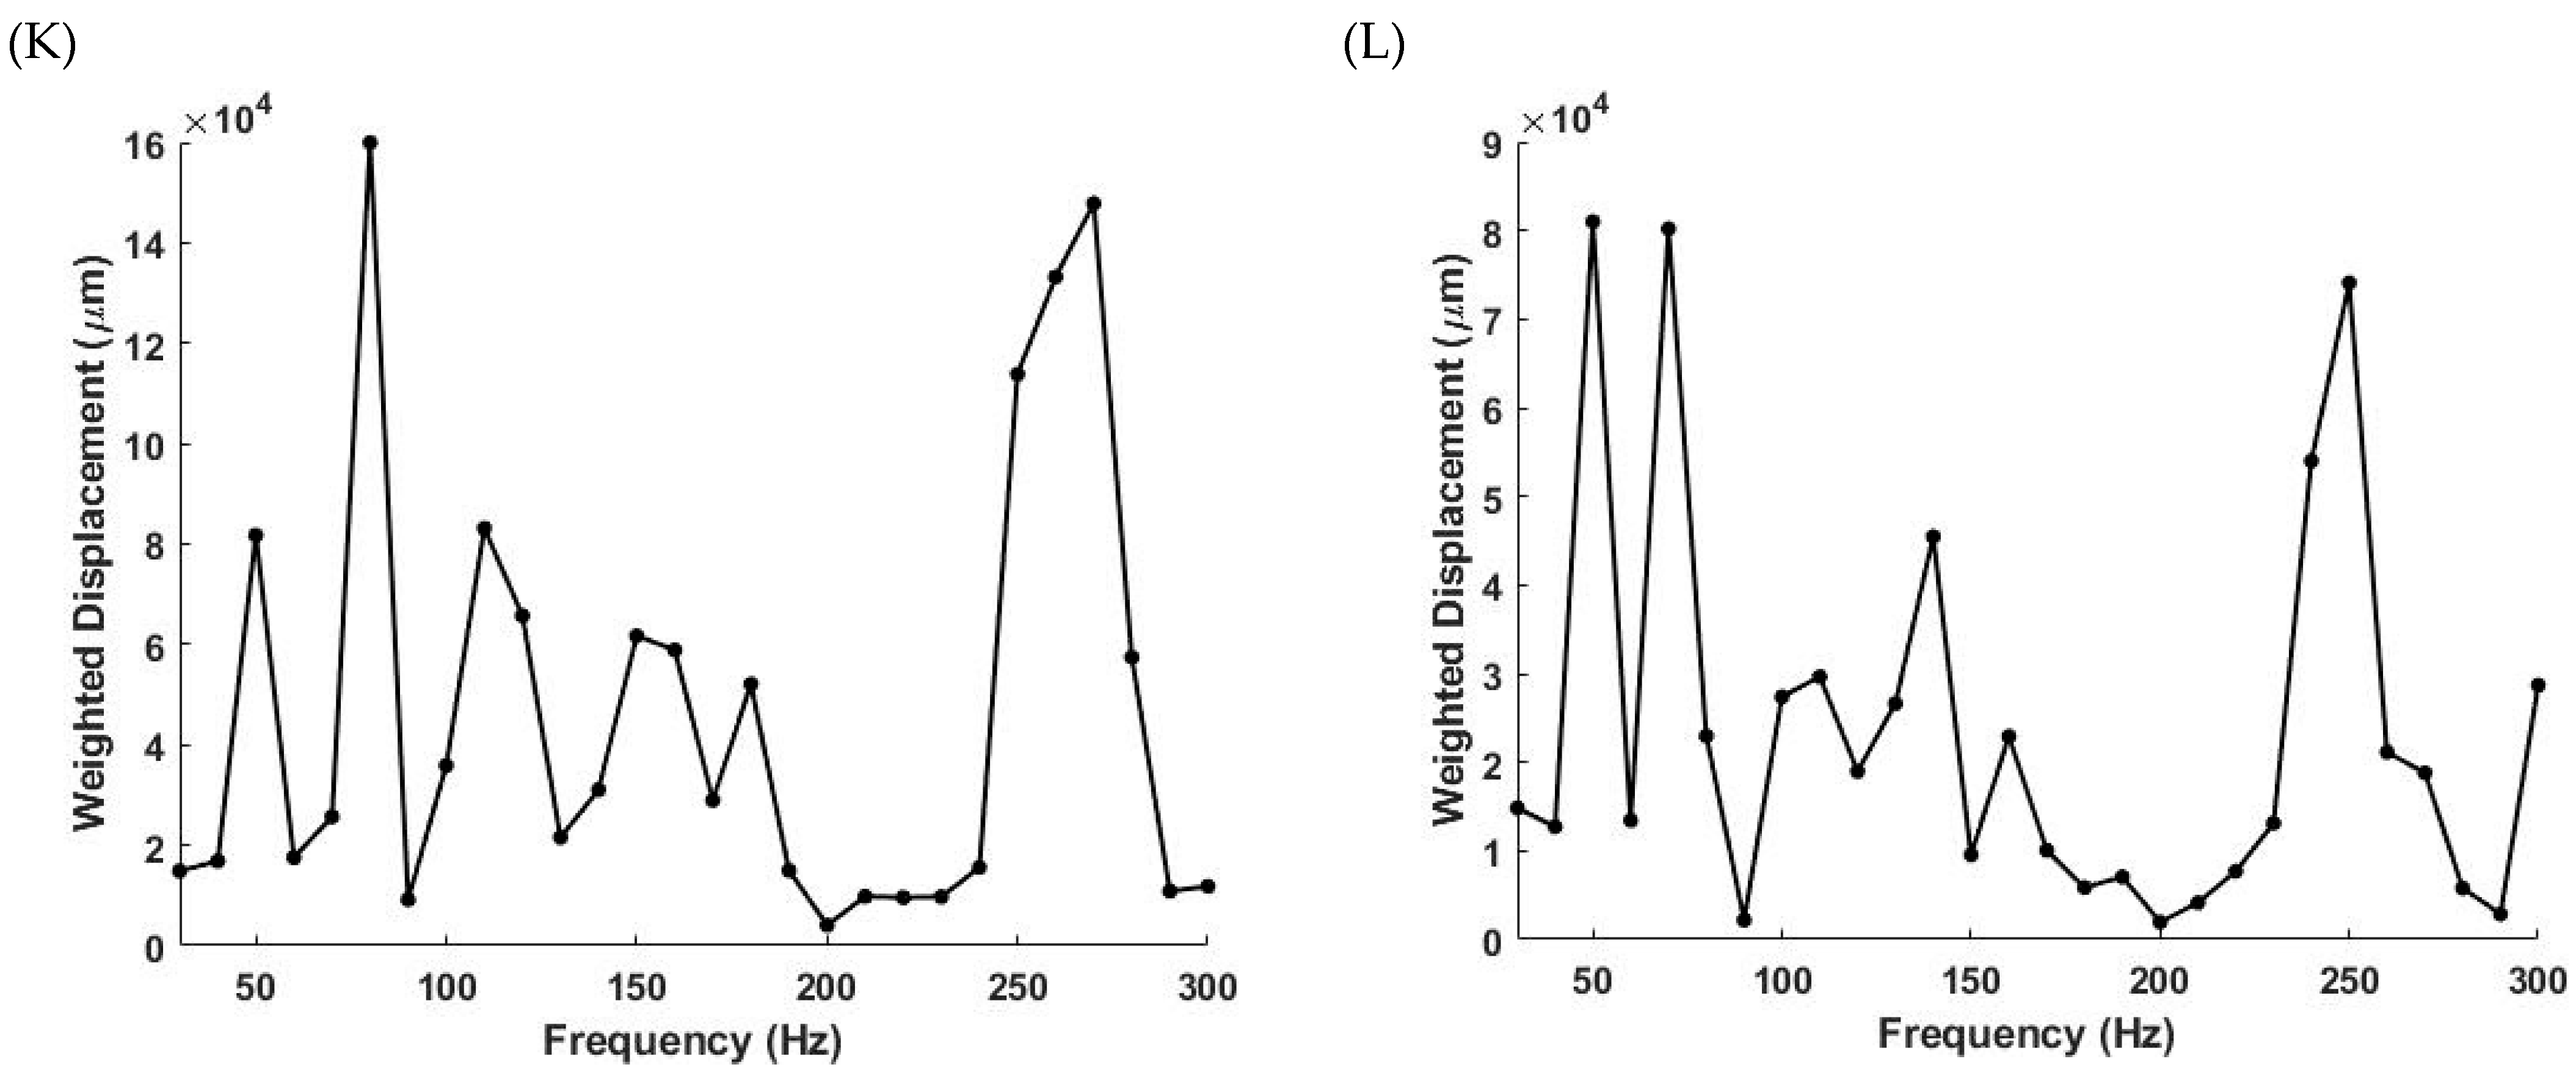

2.2. OCT Images and Scans of Pixel Intensity Versus Depth Measurements

2.3. Measurement of Resonant Frequency and the Elastic Modulus

3. Results

4. Discussion

4.1. The 80 Hz Peak

4.2. The 130 Hz Peak

4.3. The 260 Hz Peak